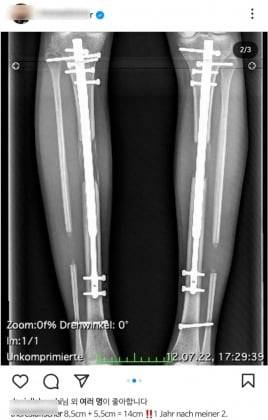

10일(현지시간) 뉴욕포스트 등 외신에 따르면 최근 모델 테레지아 피셔(31)는 리얼리티쇼 '셀러브리티 빅브라더' 독일판에 출연해 사지 연장술을 2차례 받았다고 고백했다. 피셔는 수술비로 12만4000달러(1억6400만원)를 지불했고, 물리 치료비와 약값 등을 포함하면 16만달러(2억1200만원)를 냈다고 덧붙였다.

두 번의 수술을 거쳐 169cm에서 183cm로 늘었다는 게 그의 설명이다. 다리가 14cm나 길어진 탓에 수술 후 피셔는 '긴 다리'로 유명한 모델이 됐다. 그는 "(수술 후) 더 많은 모델 제안이 들어왔고, 새로운 남자친구도 생겼고, 팔로워도 (10만명 가까이) 늘었다"고 전했다.

사지 연장술은 팔과 다리 등 뼈의 길이를 인공적으로 늘리는 수술이다. 흔히 키 높이 수술이라고 알려졌지만, 원래 수술의 목적은 선천적 기형이나 질병, 사고 등으로 인해 발생한 다리뼈 변형을 교정하거나, 양다리의 길이가 지나치게 차이가 날 경우 길이를 맞추는 것이다.

전문가들에 따르면 사지 연장술은 질병 치료 목적이 미용 목적으로 변질한 수술 중 하나이기도 하다. 수술의 기본 원리는 인위적으로 골절을 일으켜 뼈가 다시 붙는 과정에서 뼈를 조금씩 잡아 늘이는 것. 교정 중에 뼈가 다시 부러져 병원에 실려 가는 경우도 있다.

게다가 허벅지나 종아리뼈에 기구를 박아 놓은 뒤 3개월간 시술을 이어가야 하는 탓에, 감염으로 인한 부작용이 발생할 확률도 높다. 심할 경우엔 수술 후 근육괴사나 구획증후군, 신경 손상 등 후유증에 시달리기 쉽다. 합병증은 주로 늘어나는 뼈의 길이만큼 연부 조직이 성장하지 못해 생긴다. 연부 조직은 신경, 근육, 혈관 관절 등에 해당하며, 신경마비, 근육 구축, 혈관 폐쇄, 관절 운동 제한 등이 일반적인 합병증으로 알려졌다.

최근 사지 연장술 기술의 발달로 보통 수술 후 5-6개월 차가 되면 걸을 수 있는 것으로 알려져 있다. 1년 차가 되면 뛸 수 있는 수준이 되고, 2년 차 이후 내부 고정 장치를 제거할 때쯤이 되면 수술 전과 다를 바 없는 다리 상태가 된다고 한다.